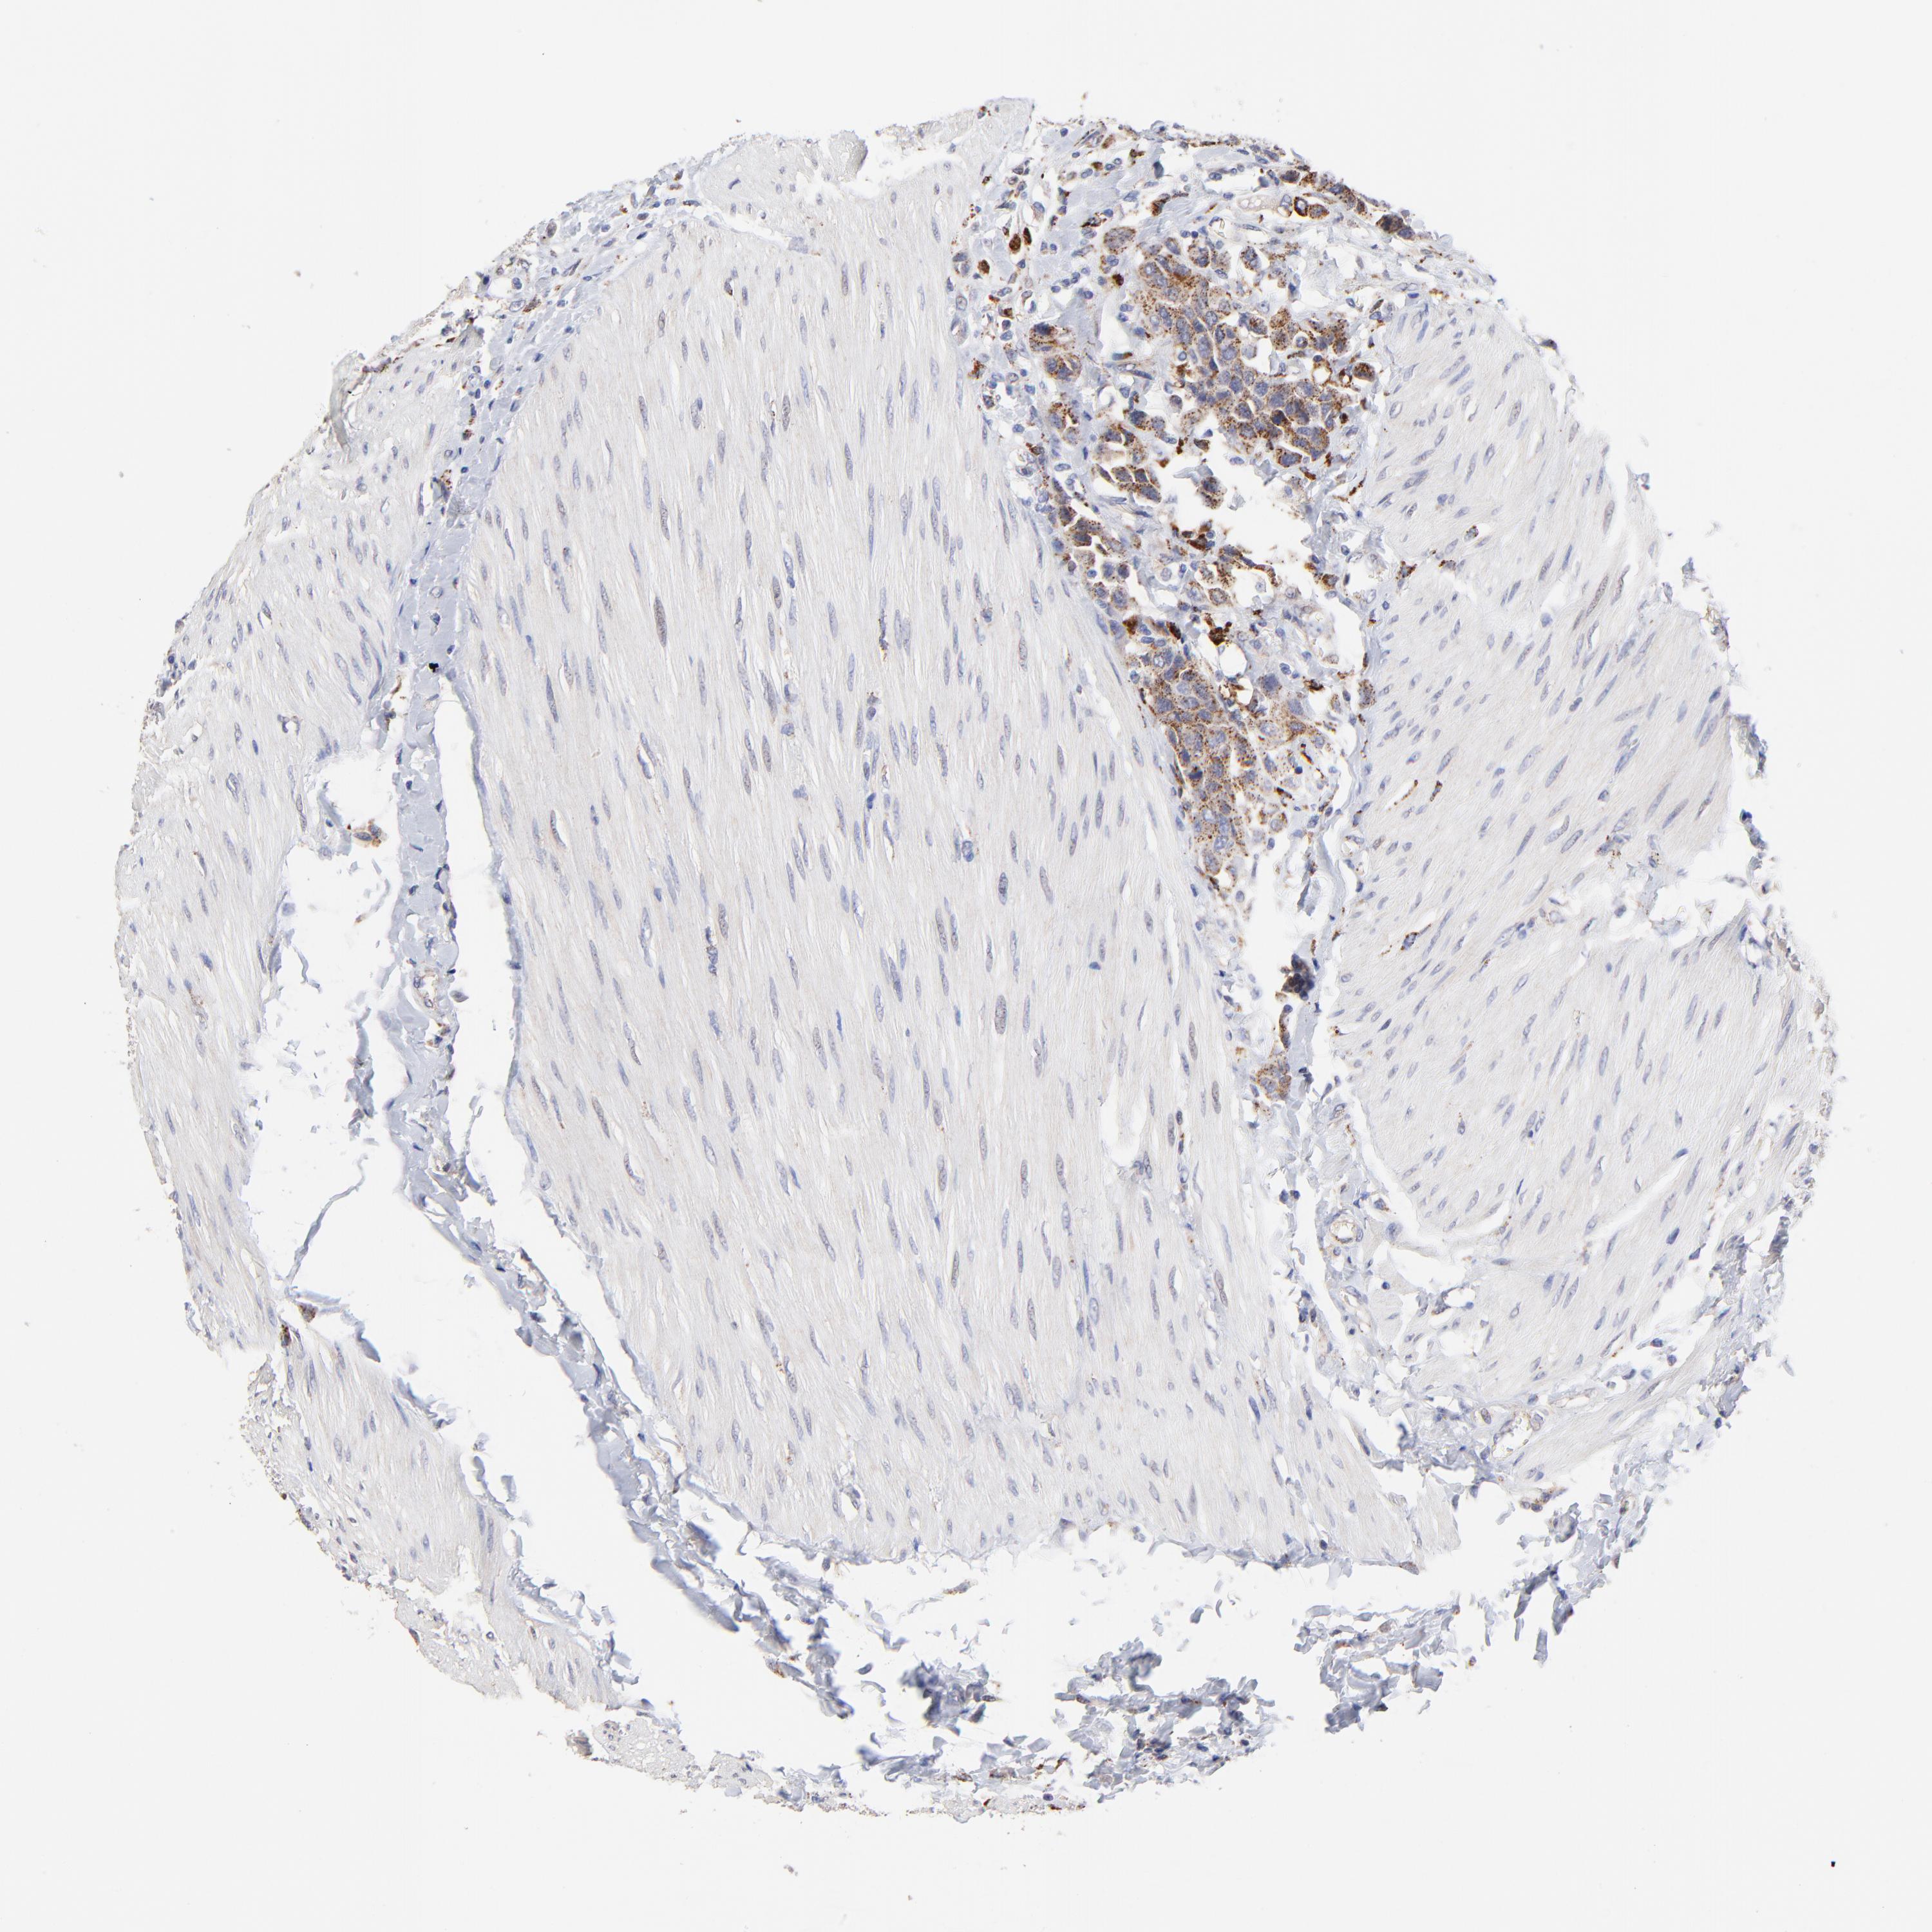

UROTHELIAL CANCER - Protein expressioni

A mouse-over function shows sample information and annotation data. Click on an image to view it in a full screen mode. Samples can be filtered based on level of antibody staining by selecting one or several of the following categories: high, medium, low and not detected. The assay and annotation is described here.

Note that samples used for immunohistochemistry by the Human Protein Atlas do not correspond to samples in the TCGA dataset.

Antibody stainingi

Antibody staining in the annotated cell types in the current human tissue is reported as not detected, low, medium, or high, based on conventional immunohistochemistry profiling in selected tissues. This score is based on the combination of the staining intensity and fraction of stained cells.

Each image is clickable and will lead to virtual microscopy that enables deeper exploration of all samples and also displays staining intensity scores, fraction scores and subcellular localization as well as patient and tissue information for each sample.

Antibody HPA003005

Urothelial carcinoma, High grade

Urothelial carcinoma, Low grade